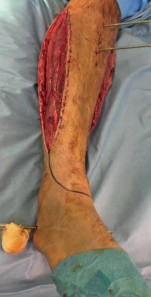

The patho-epidemiology of these injuries is inextricably linked to the incidence of acute compartment syndrome. High-energy axial loads result in rapid swelling, hemorrhage, and edema within the unyielding fascial compartments of the leg. As demonstrated in our reference case, clinical examination often reveals a tense, swollen limb necessitating an immediate four-compartment fasciotomy. The dual-incision technique remains the standard of care to decompress the anterior, lateral, superficial posterior, and deep posterior compartments. The presence of fasciotomy wounds further complicates the surgical approach for definitive internal fixation, requiring strict adherence to the principles of damage control orthopedics (DCO).

In the setting of acute compartment syndrome, the presence of fasciotomy wounds fundamentally alters the surgical timeline. The primary goal is the preservation of limb viability through immediate decompression. Once the external fixator is applied, the fasciotomy wounds are typically managed with negative pressure wound therapy (NPWT) or vessel loops (shoelace technique) to facilitate gradual closure. Definitive internal fixation must be delayed until the soft tissue envelope is deemed capable of withstanding further surgical insult, which often takes 10 to 21 days.

Soft Tissue Management and Approach Selection

The surgical approach must be carefully orchestrated, particularly in a patient with pre-existing fasciotomy incisions. If an anterolateral approach is selected, the incision is typically centered over the interval between the tibialis anterior and the extensor hallucis longus (EHL), or between the EHL and the extensor digitorum longus (EDL). The superficial peroneal nerve must be meticulously identified and protected, as it often crosses the surgical field in the distal third of the leg. The anterior tibial artery and deep peroneal nerve are retracted laterally with the EDL.

If a medial approach is utilized, the incision is made just medial to the tibial crest, avoiding the saphenous vein and nerve. The full-thickness fasciocutaneous flap is elevated off the periosteum to minimize devascularization. In cases where compartment syndrome fasciotomies have been performed, the surgeon must often incorporate the existing traumatic or surgical incisions into the definitive surgical approach to avoid creating narrow skin bridges that are prone to necrosis.